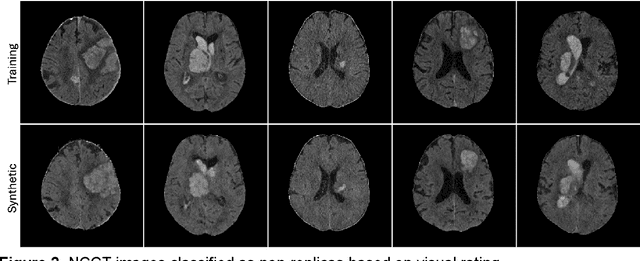

Abstract:Despite the potential of synthetic medical data for augmenting and improving the generalizability of deep learning models, memorization in generative models can lead to unintended leakage of sensitive patient information and limit model utility. Thus, the use of memorizing generative models in the medical domain can jeopardize patient privacy. We propose a framework for identifying replicas, i.e. nearly identical copies of the training data, in synthetic medical image datasets. Our REpLIca deteCTion (RELICT) framework for medical image generative models evaluates image similarity using three complementary approaches: (1) voxel-level analysis, (2) feature-level analysis by a pretrained medical foundation model, and (3) segmentation-level analysis. Two clinically relevant 3D generative modelling use cases were investigated: non-contrast head CT with intracerebral hemorrhage (N=774) and time-of-flight MR angiography of the Circle of Willis (N=1,782). Expert visual scoring was used as the reference standard to assess the presence of replicas. We report the balanced accuracy at the optimal threshold to assess replica classification performance. The reference visual rating identified 45 of 50 and 5 of 50 generated images as replicas for the NCCT and TOF-MRA use cases, respectively. Image-level and feature-level measures perfectly classified replicas with a balanced accuracy of 1 when an optimal threshold was selected for the NCCT use case. A perfect classification of replicas for the TOF-MRA case was not possible at any threshold, with the segmentation-level analysis achieving a balanced accuracy of 0.79. Replica detection is a crucial but neglected validation step for the development of generative models in medical imaging. The proposed RELICT framework provides a standardized, easy-to-use tool for replica detection and aims to facilitate responsible and ethical medical image synthesis.